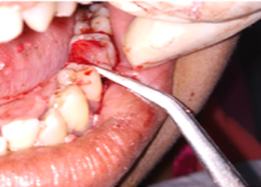

Post-OP Clinical View